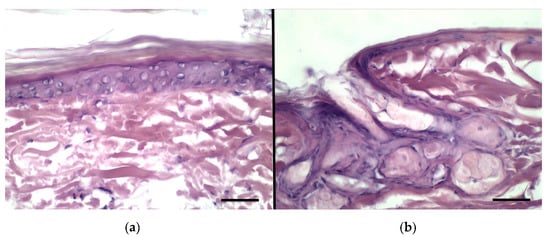

The experiment was performed using the vertical diffusion Franz cells in order to compare the permeation ability of the three different vesicles loaded with BRB inside the skin layers and across the skin, as well as to predict BRB absorption. The permeation study was carried out using the finite dose technique, namely applying doses normally used in clinical conditions. In fact, human exposure to chemicals by topical application of drug is usually of few milligrams of drug per square centimeter of skin, 2–5 mg/cm2 [41]. As a first step of our investigation, a conventional histological analysis of the rabbit ear skin samples taken after the permeation studies were carried out (Figure 8). The investigation allowed to exclude the occurrence of major morphological alterations due to the sampling and handling procedures, thus accounting for reliability of the permeation assay.

Figure 8.

Histological features of rabbit ear skin after the permeation test: (a) epidermis, (b) hair follicle and sebaceous gland. Bars = 50 μm.